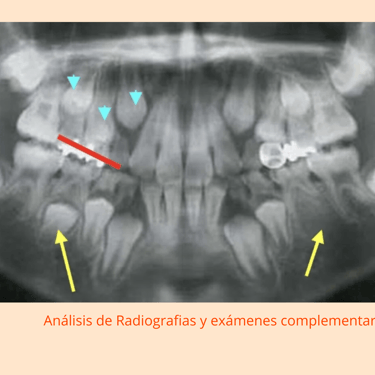

Evaluación Inicial: Examen y radiografías para evaluar el crecimiento y desarrollo dental.

Instrumentos: Radiografías, modelos dentales, exploradores.